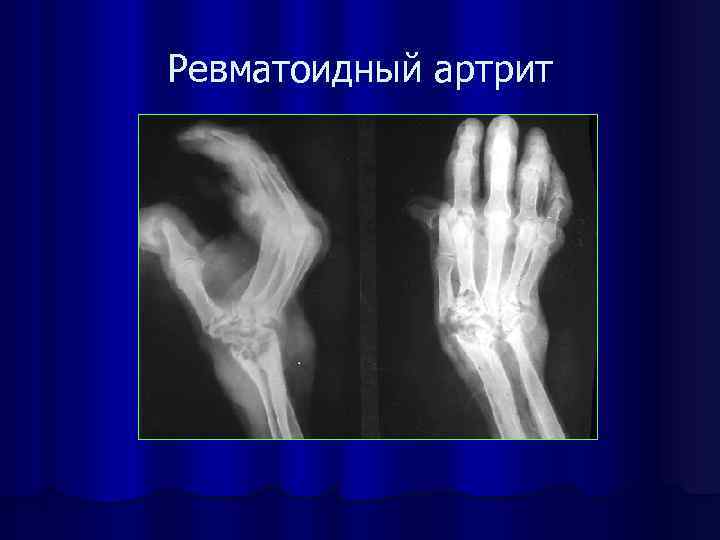

Ревматоидный артрит

Рентгеносемиотика воспалительного поражения сустава l l Сужение рентгеновской суставной щели Истончение или разрушение замыкающей костной пластинки в обоих суставных концах Остеопороз суставных концов Деструктивные очаги в подхрящевом (субхондральном) слое губчатого костного вещества эпифизов